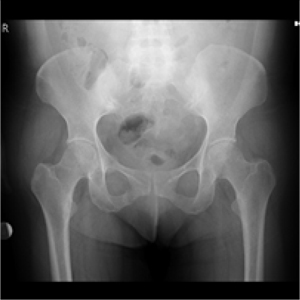

A 48 years-old female patient was admitted to our polyclinic affected by right hip and groin pain for two months without trauma history. The symptomatology increased with daily activities and effort, however, it decreased with rest. Attending to her personal history, the patient did not present any illness during this period of time, she was not under treatment with steroids, and she was no under radiation exposure. Duirng this period, the patient was under treatment with non-steroid antiinflammatory drug (NSAID) without beneficial results. Due to that reason, she applied to our polyclinic several times during the last two months. Attending to the physical exploration, an antalgic gait was observed, but the patient did not need assistance devices to walk. There was not observed swelling, tenderness, warmth or color disturbs at right hip level. There was not also showed range of motion (ROM) limitation at the hip joint. However, the patient reported pain duringhip joint movements. Lasegue test as well as sensorial exploration on lower extremities did not showed any disturbs. According to the physical exploration, a pelvic x-radiograph study was requested showing a right pubic ramus stress fracture (Figure 1).

Figure 1: Radiograph showing right superior and inferior stress fracture.